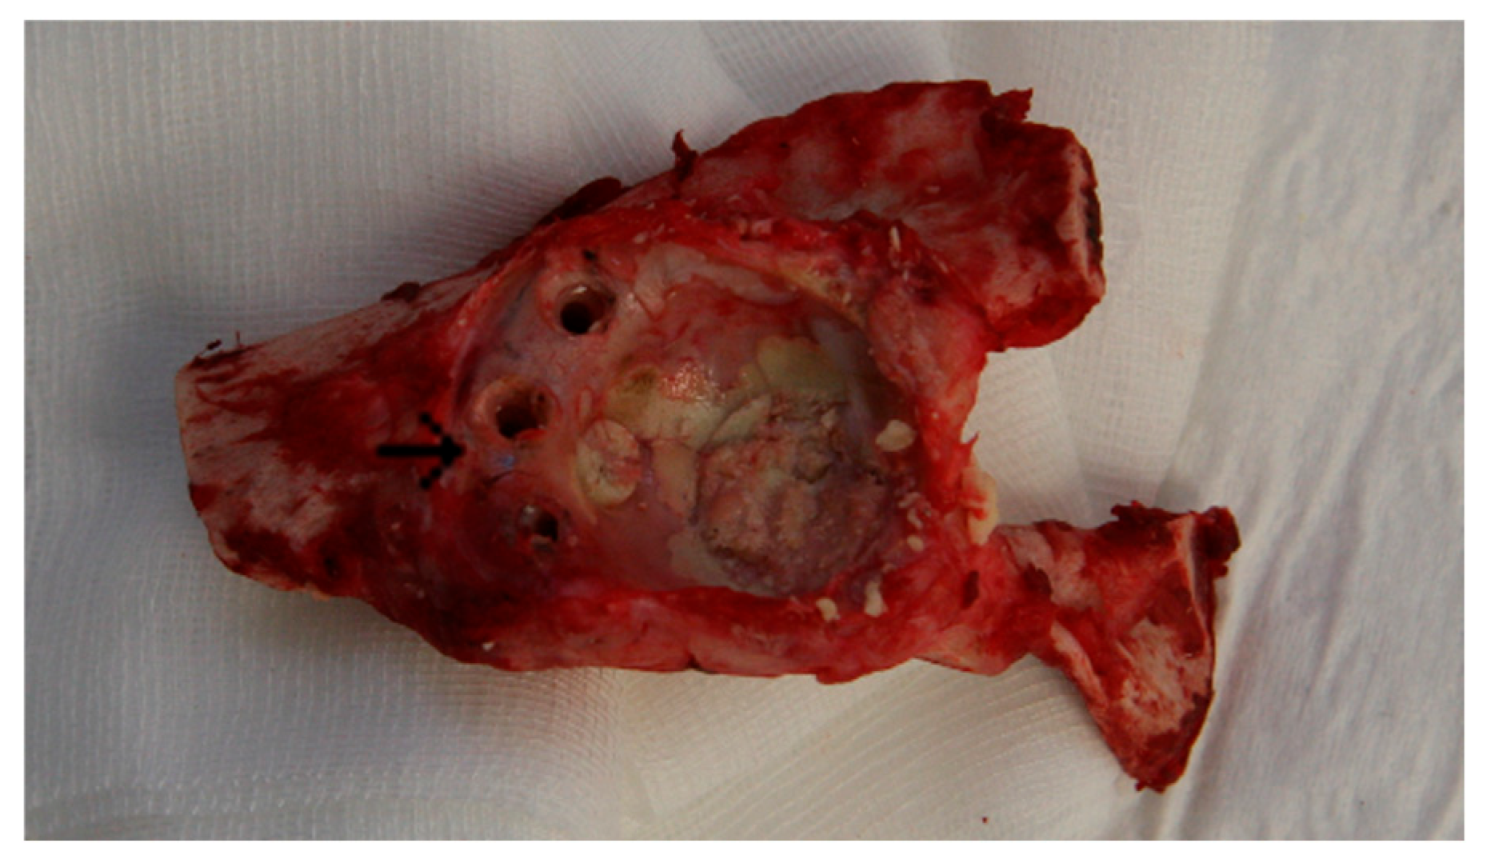

3.1. Animal Experiment: Macroscopic Assessment